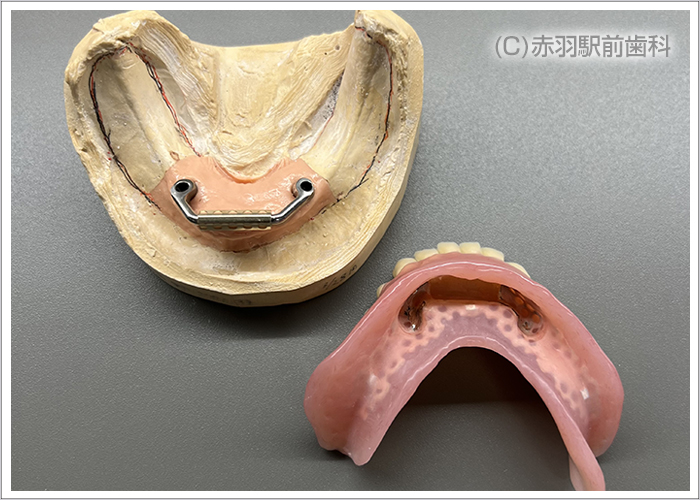

歯を全て失った患者様です。上下とも総入れ歯を入れていました。入れ歯が安定しないので食べるものも制限され会話もしづらい状態です。

CTデータから事前に3Dプリンターで、患者様の実寸代の顎骨模型を作成しておいて手術前にシミュレーションで担当医がインプラント埋入とSRAアバットを装着しておきました。画像は下顎の模型です。両サイドのインプラントはオールオン4特有の傾斜埋入をしてあります。

シミュレーション通りの位置にインプラント手術を完了しました。上下ともに両サイドのインプラントはオールオン4特有の傾斜埋入をしています。

インプラント手術完了後にSRAアバットを装着した状態の口腔内です。固定式の仮歯が当日に入ります。